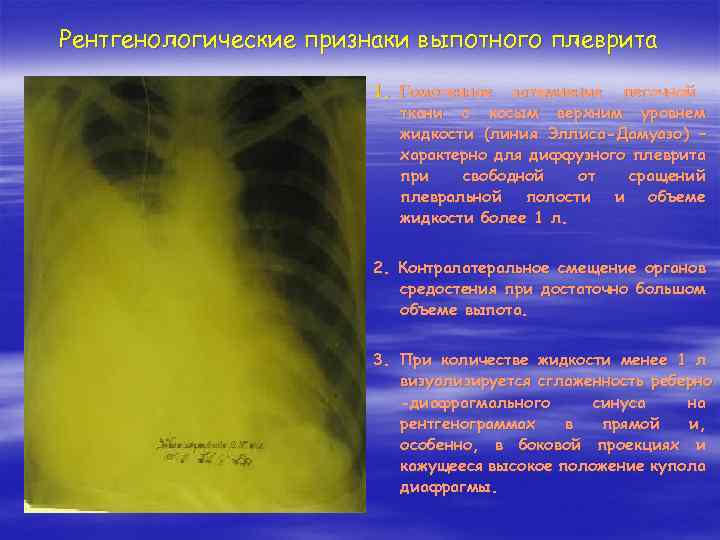

Ячеистая деформация легочного рисунка: медицинская визуализация